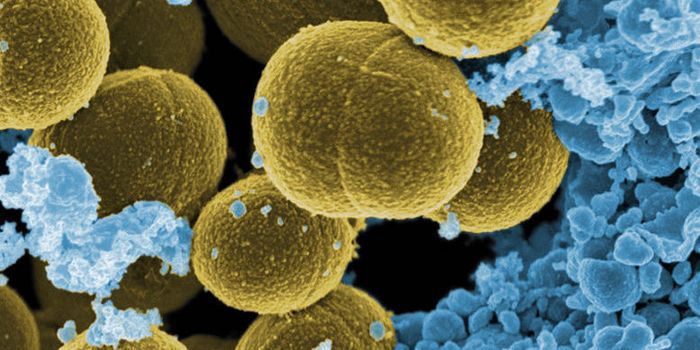

SEP 30, 2016MicrobiologyCurrent hospital laboratory testing is not great at identifying bacterial infections; it can take precious time and reso ...

FEB 14, 2016Clinical & Molecular DXIn the clinical setting, wound infections can significantly delay recovery time and even become life threatening. Early ...